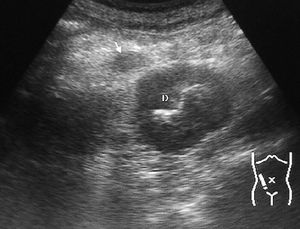

La púrpura de Schönlein-Henoch es una enfermedad autoinmune sistémica provocada por el depósito de complejos inmunes en los pequeños vasos condicionando una alteración en la permeabilidad. Esto se traduce en un rash purpúrico, glomerulonefritis y hemorragia en el tracto gastrointestinal. En la ecografía se puede ver un engrosamiento de la pared intestinal por el hematoma mural con edema mesentérico en la TC13 (fig.6).

Fig. 6--Hematoma de pared. Ecografía que muestra un engrosamiento mural homogéneo de la tercera porción duodenal (D) en un paciente con púrpura de Schönlein-Henoch y dolor abdominal.